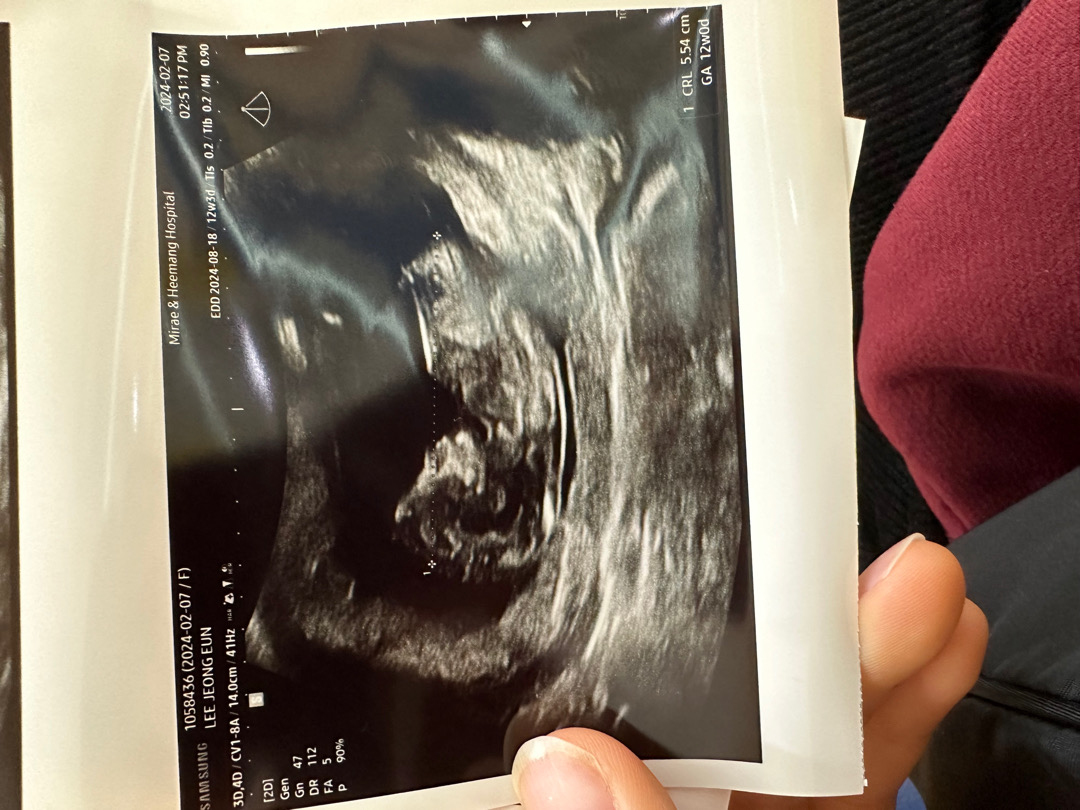

12주3일차 각도법좀 부탁드려요~

건강하다고 하니 성별이 궁금하네요~각도법 고수님들 봐주세요ㅎㅎ